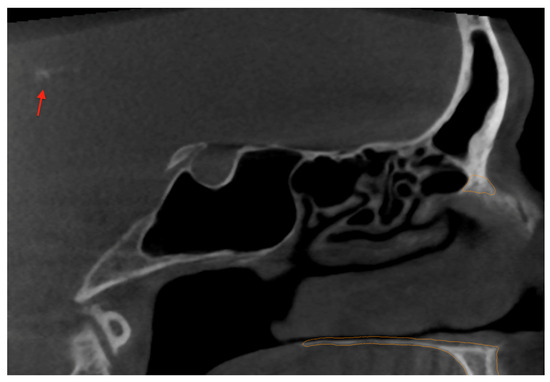

Artificial Intelligence-Assisted Segmentation of a Falx Cerebri Calcification on Cone-Beam Computed Tomography: A Case Report

2. Case Report and AI Application